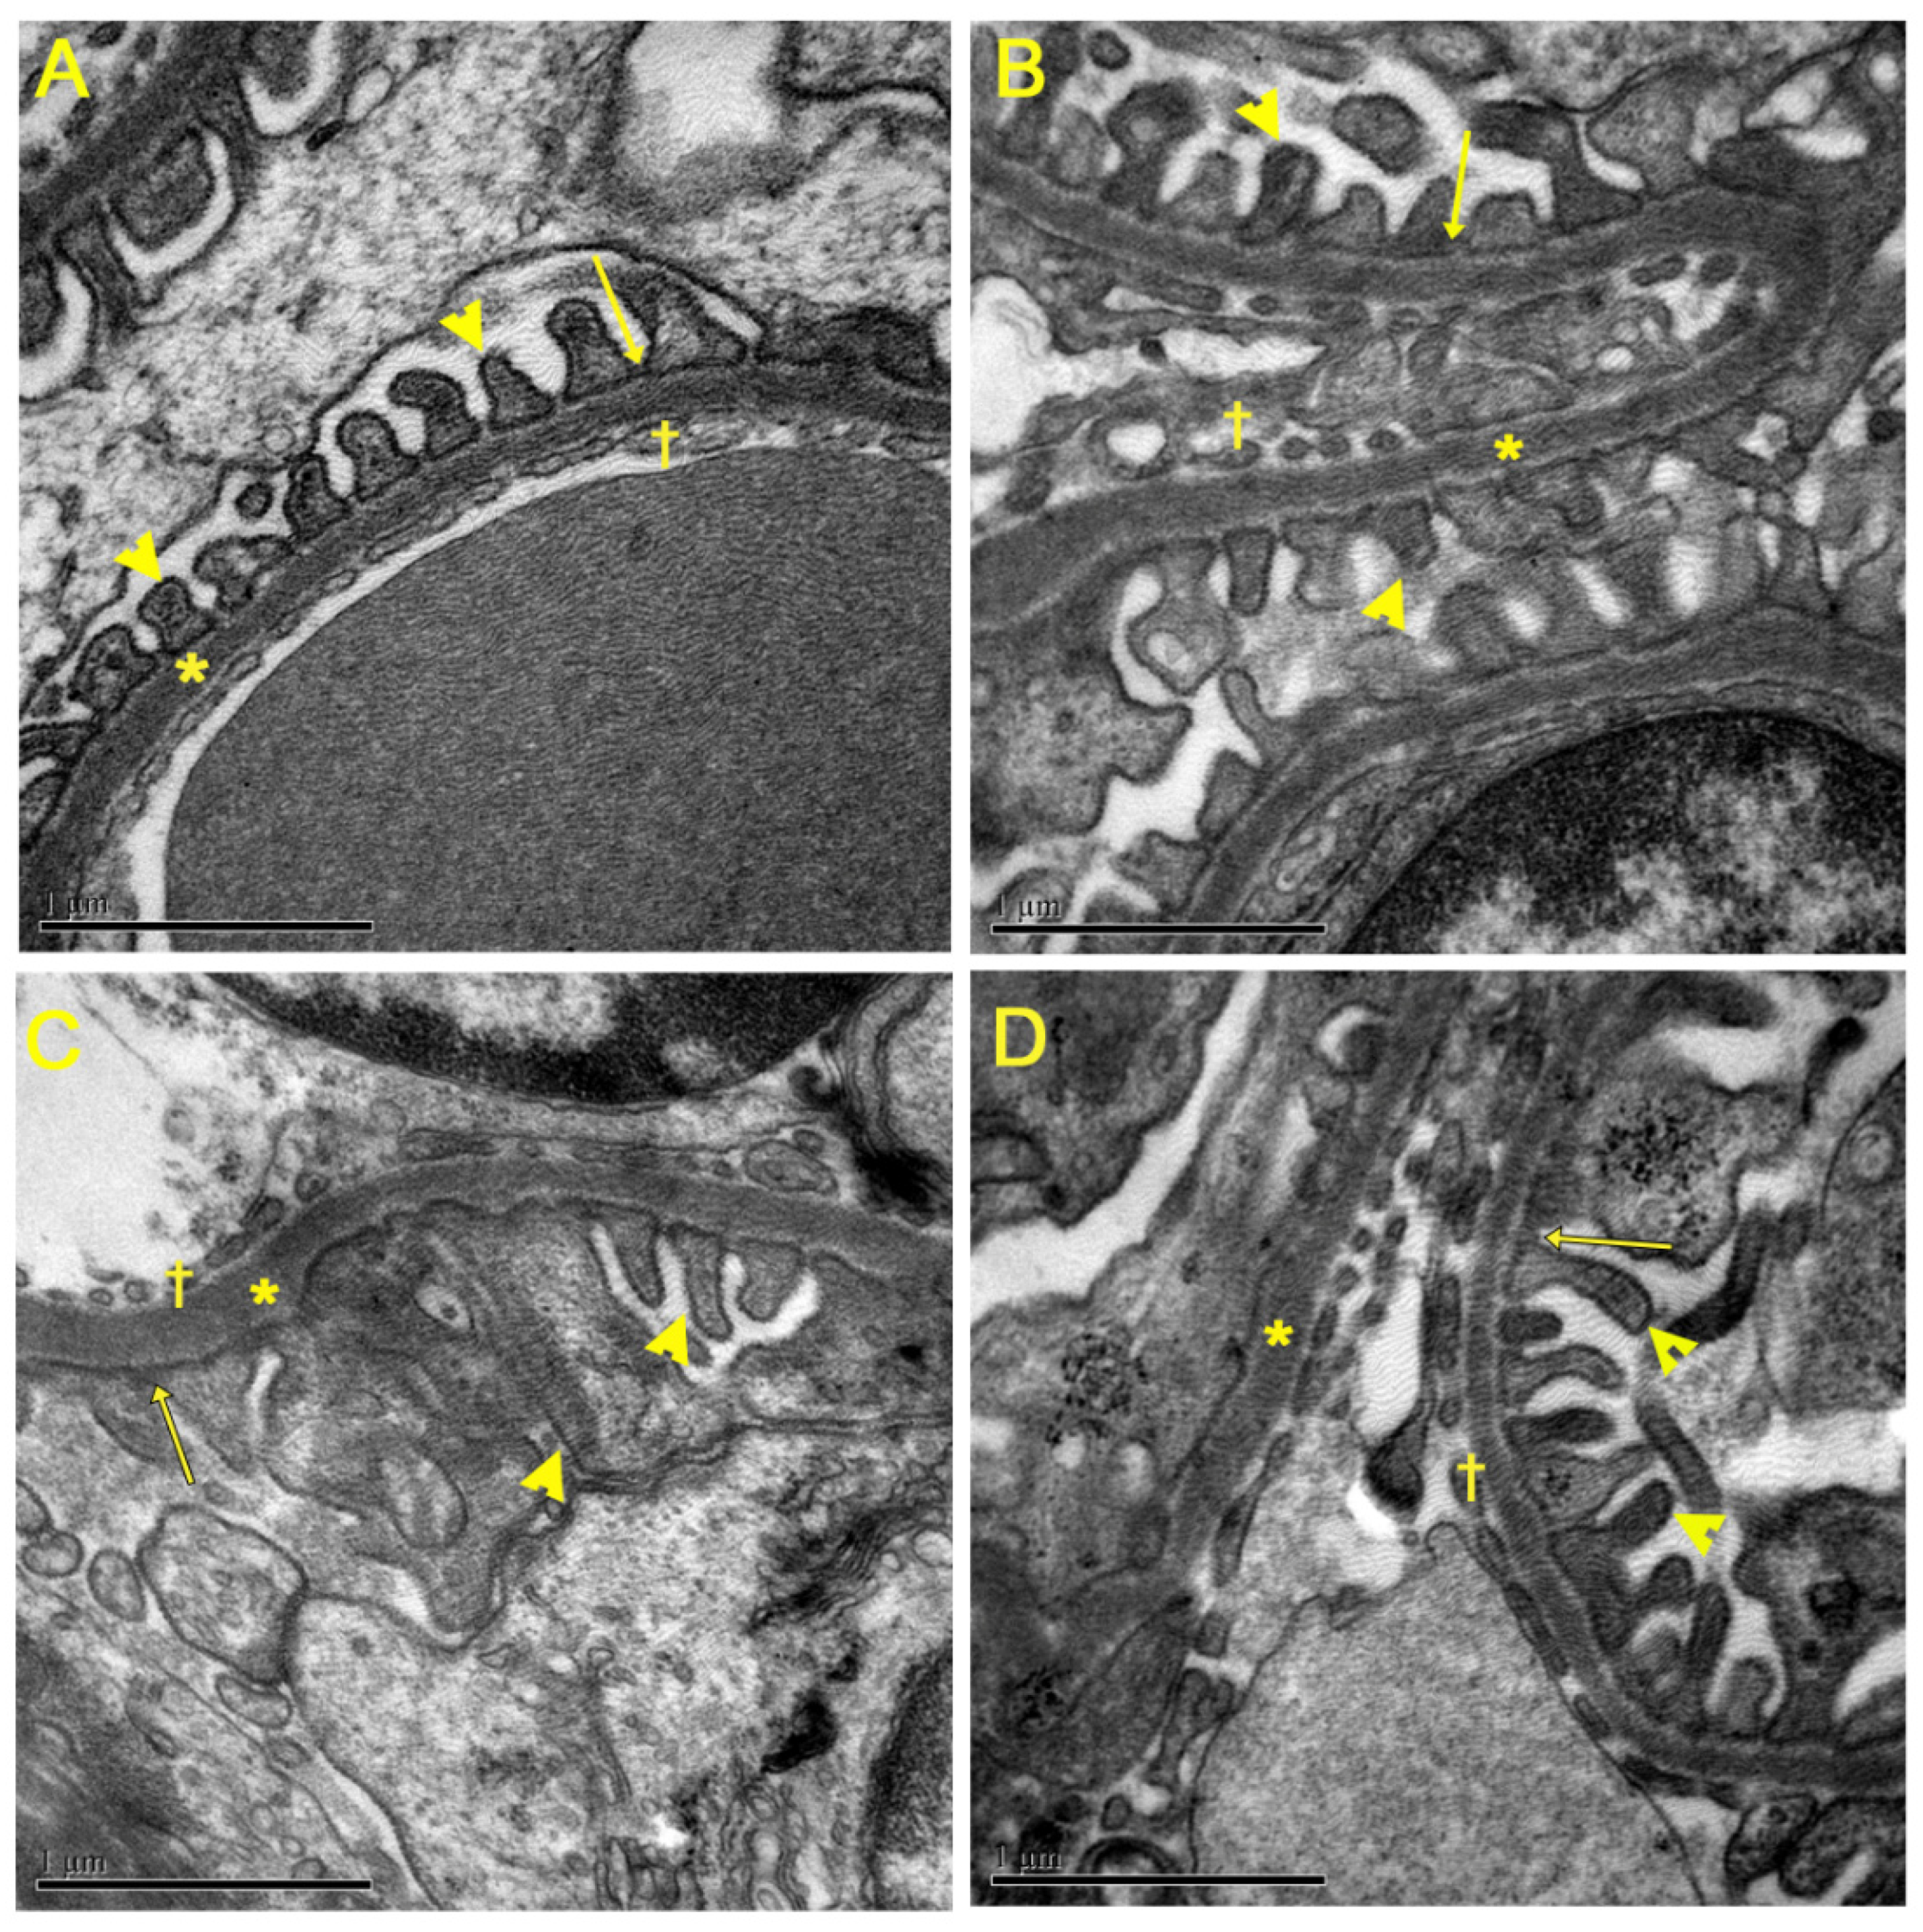

3.5. Evaluation of Renal Ultrastructure